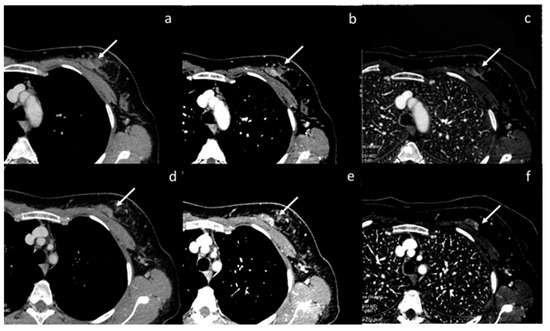

- Wang, X.; Liu, D.; Jiang, S.; Zeng, X.; Li, L.; Yu, T.; Zhang, J. Subjective and Objective Assessment of Monoenergetic and Polyenergetic Images Acquired by Dual-Energy CT in Breast Cancer. Korean J. Radiol. 2021, 22, 502–512. [Google Scholar] [CrossRef]

- Volterrani, L.; Gentili, F.; Fausto, A.; Pelini, V.; Megha, T.; Sardanelli, F.; Mazzei, M.A. Dual-Energy CT for Locoregional Staging of Breast Cancer: Preliminary Results. Am. J. Roentgenol. 2020, 214, 707–714. [Google Scholar] [CrossRef] [PubMed]

| Wang et al. [56] Retrospective study | China | To objectively and subjectively assess and compare the characteristics of mono-energetic images and poly-energetic images acquired by DECT of patients with breast cancer | 42 | SOMATOM Drive, Siemens Healthineers No C.I. | Reconstructions at low keV in the venous phase acquired by DECT improved the objective and subjective assessment of lesion conspicuity in patients with malignant breast lesions. |

| Volterrani et al. [57] Retrospective study | Italy | To demonstrate the feasibility of DECT for locoregional staging of breast cancer and differentiation of tumor histotypes | 31 | Discovery CT 750 HD, GE Healthcare No C.I. | DECT is feasible and seems to be a reliable tool for locoregional staging of breast cancer. |

| Moon et al. [58] Retrospective study | South Korea | To evaluate the predictive value of VMI by assessing tumor conspicuity on dual-layer spectral detector CT and correlate tumor conspicuity on VMI with prognostic biomarkers in patients with breast cancer | 64 | IQon Spectral CT, Philips Health System No C.I. | VMI40DEL may be useful in the diagnosis of breast cancers due to higher tumor conspicuity and better enhancement than VMI40ART. VMI40ART may be beneficial for the prediction of poor breast cancer prognoses. |